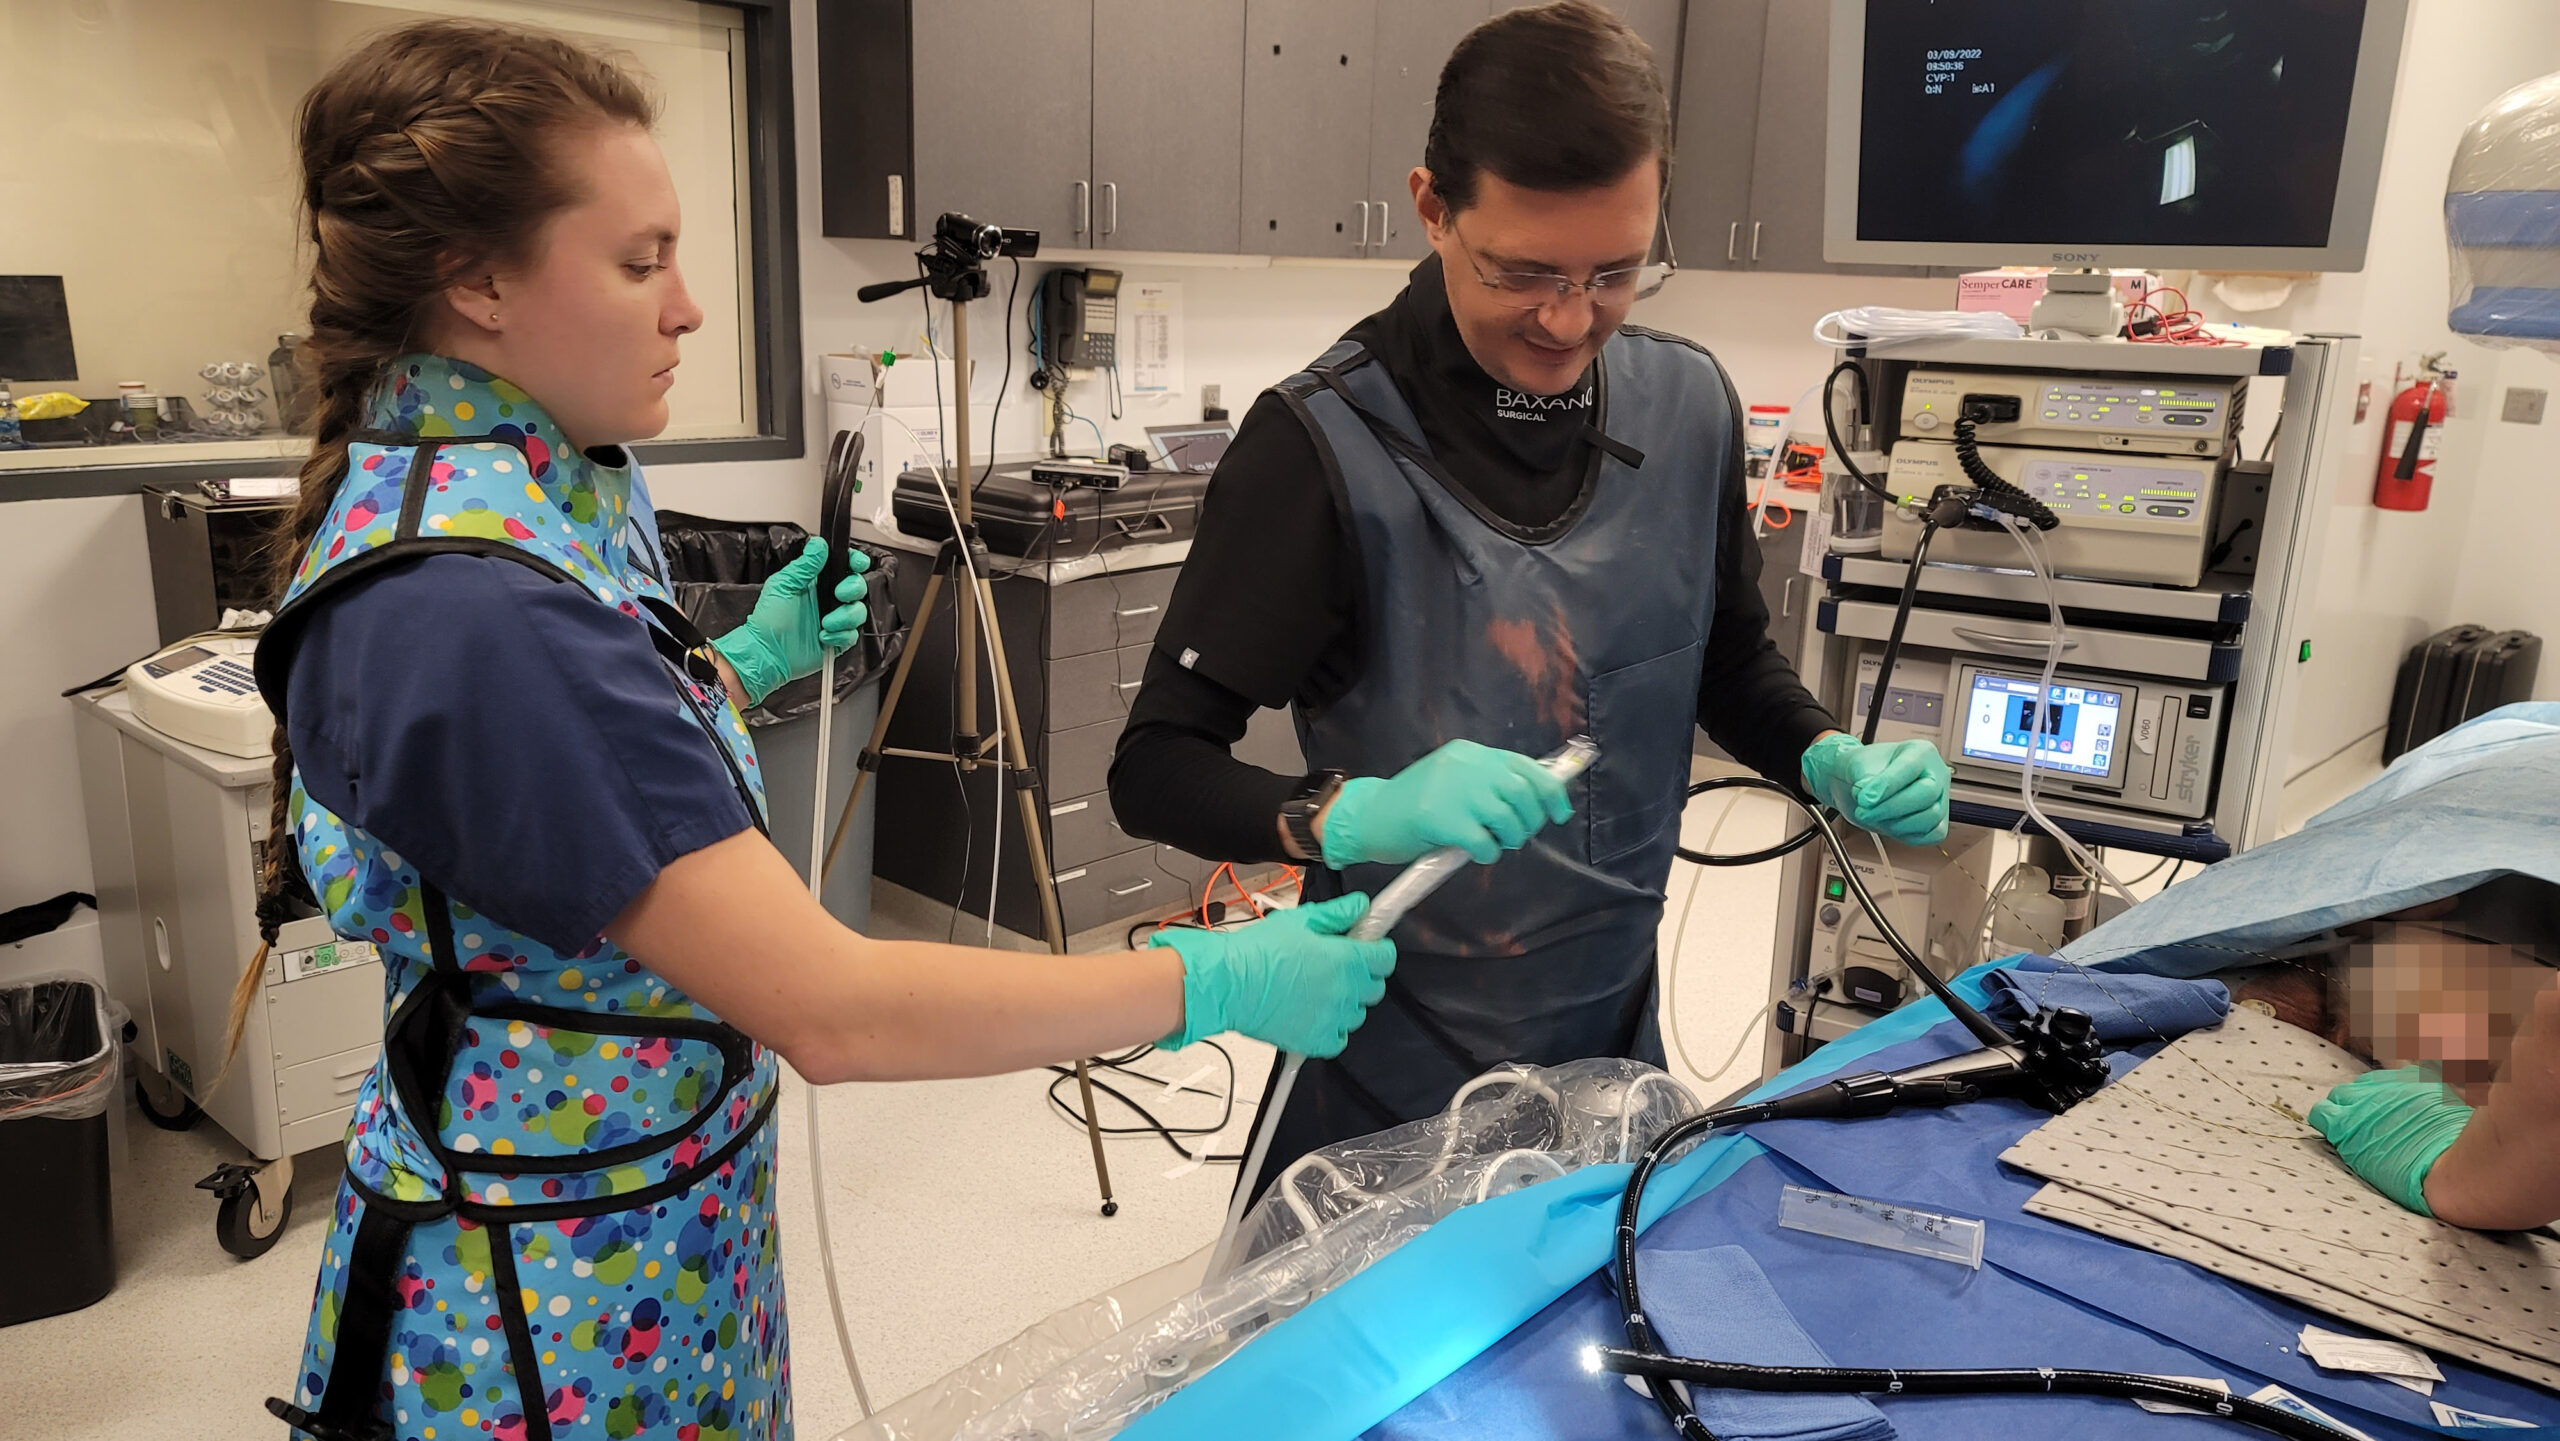

A fully incisionless procedure

The first cut-free endoscopic treatment for diabesity, ForePass ® is able to replicate the most common types of metabolic surgery (Roux-en-Y Gastric Bypass, RYGB, BilioPancreatic Diversion, and Sleeve Gastrectomy). The first version of our product is aimed at RYGB.

Designed to replicate metabolic surgery without any cuts to internal organs. As effective on diabetes and obesity as metabolic surgery in animals.